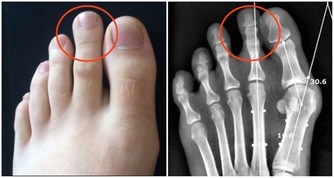

• 反復發生多發性口腔潰瘍,同時或前後伴有外生殖器潰瘍,皮膚出現痤瘡、毛囊炎,眼睛不適、視力下降,應考慮白塞氏病。

• 口腔潰瘍前後伴有脫髮,顏面部紫紅斑,關節疼痛等症狀時可能是紅斑狼瘡所致。